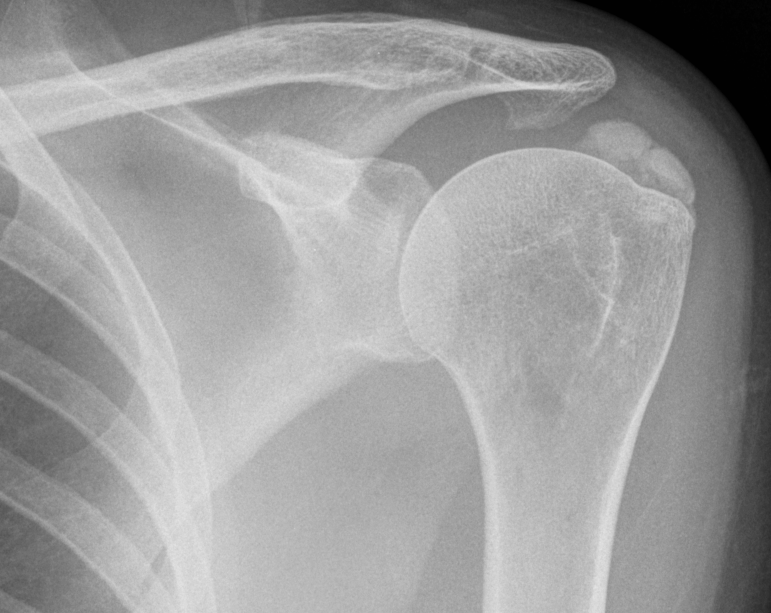

Calcific tendinopathy of supraspinatus